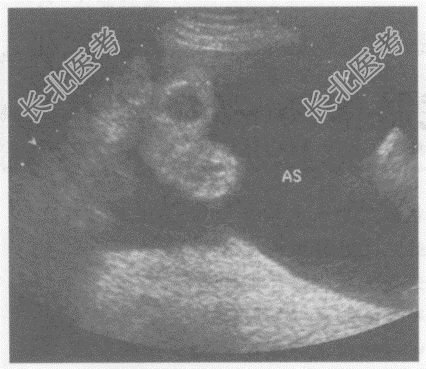

- 单项选择题临床资料:男性患者, 57岁,自诉患乙肝、肝硬化十余年, 加重月余,右上腹胀痛、纳差。

超声综合描述: 腹、盆腔、膈下可见大片状无回声区,最大深度7.3cm, 透声清亮,内见肠管浮动。

超声提示:  A、淋巴囊肿

B、腹腔积血(大量)

C、腹腔积液(大量)

D、腹腔包裹性积液

E、腹主动脉瘤